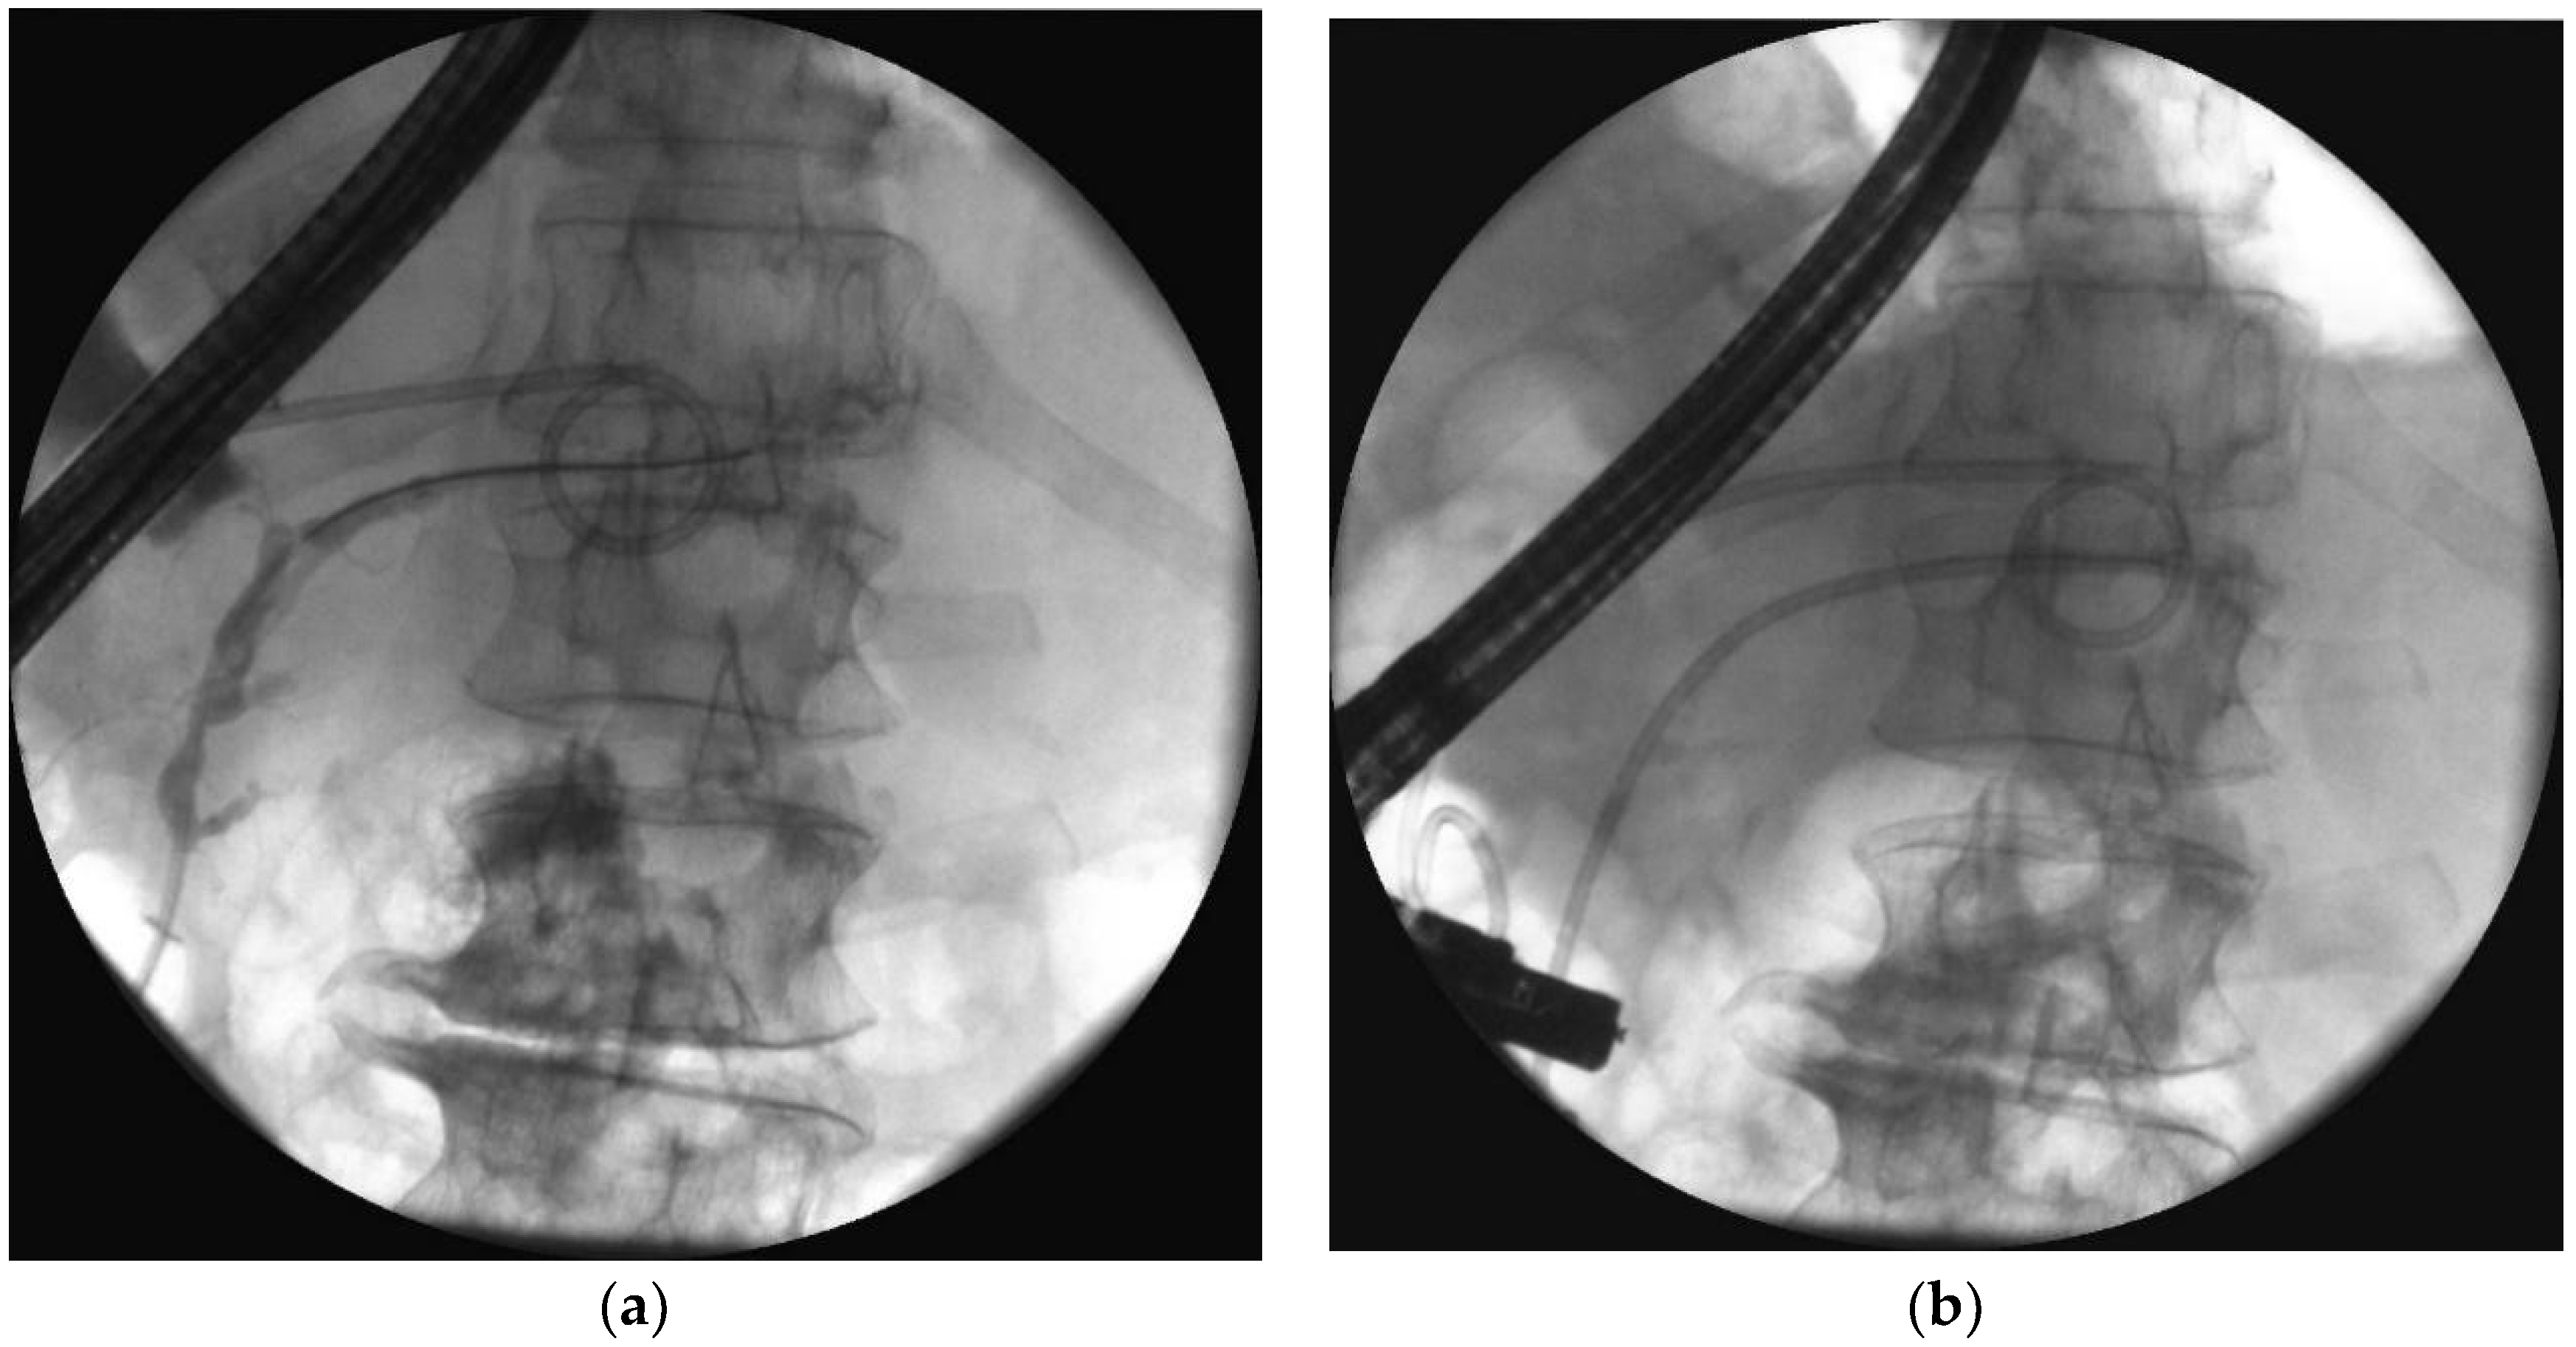

- Jagielski, M.; Smoczyński, M.; Adrych, K. Transpapillary drainage of pancreatic parenchymal necrosis. Wideochir. Inne. Tech. Maloinwazyjne 2015, 10, 491–494. [Google Scholar] [CrossRef]

- Smoczyński, M.; Jagielski, M.; Jabłońska, A.; Adrych, K. Transpapillary drainage of walled-off pancreatic necrosis- a single center experience. Wideochir. Inne. Tech. Maloinwazyjne 2015, 10, 527–533. [Google Scholar] [CrossRef] [PubMed]

- Smoczyński, M.; Jagielski, M.; Siepsiak, M.; Adrych, K. Endoscopic necrosectomy through the major duodenal papilla under fluoroscopy imaging. Arch. Med. Sci. 2018, 14, 470–474. [Google Scholar] [CrossRef] [PubMed]

| Passive transpapillary drainage | The insertion endoscopic pancreatic stent to pancreatic duct through duodenal papilla. |

| Active transpapillary drainage | Endoscopic insertion pancreatic endoprosthesis as well as nasal drain to pancreatic duct through duodenal papilla. |